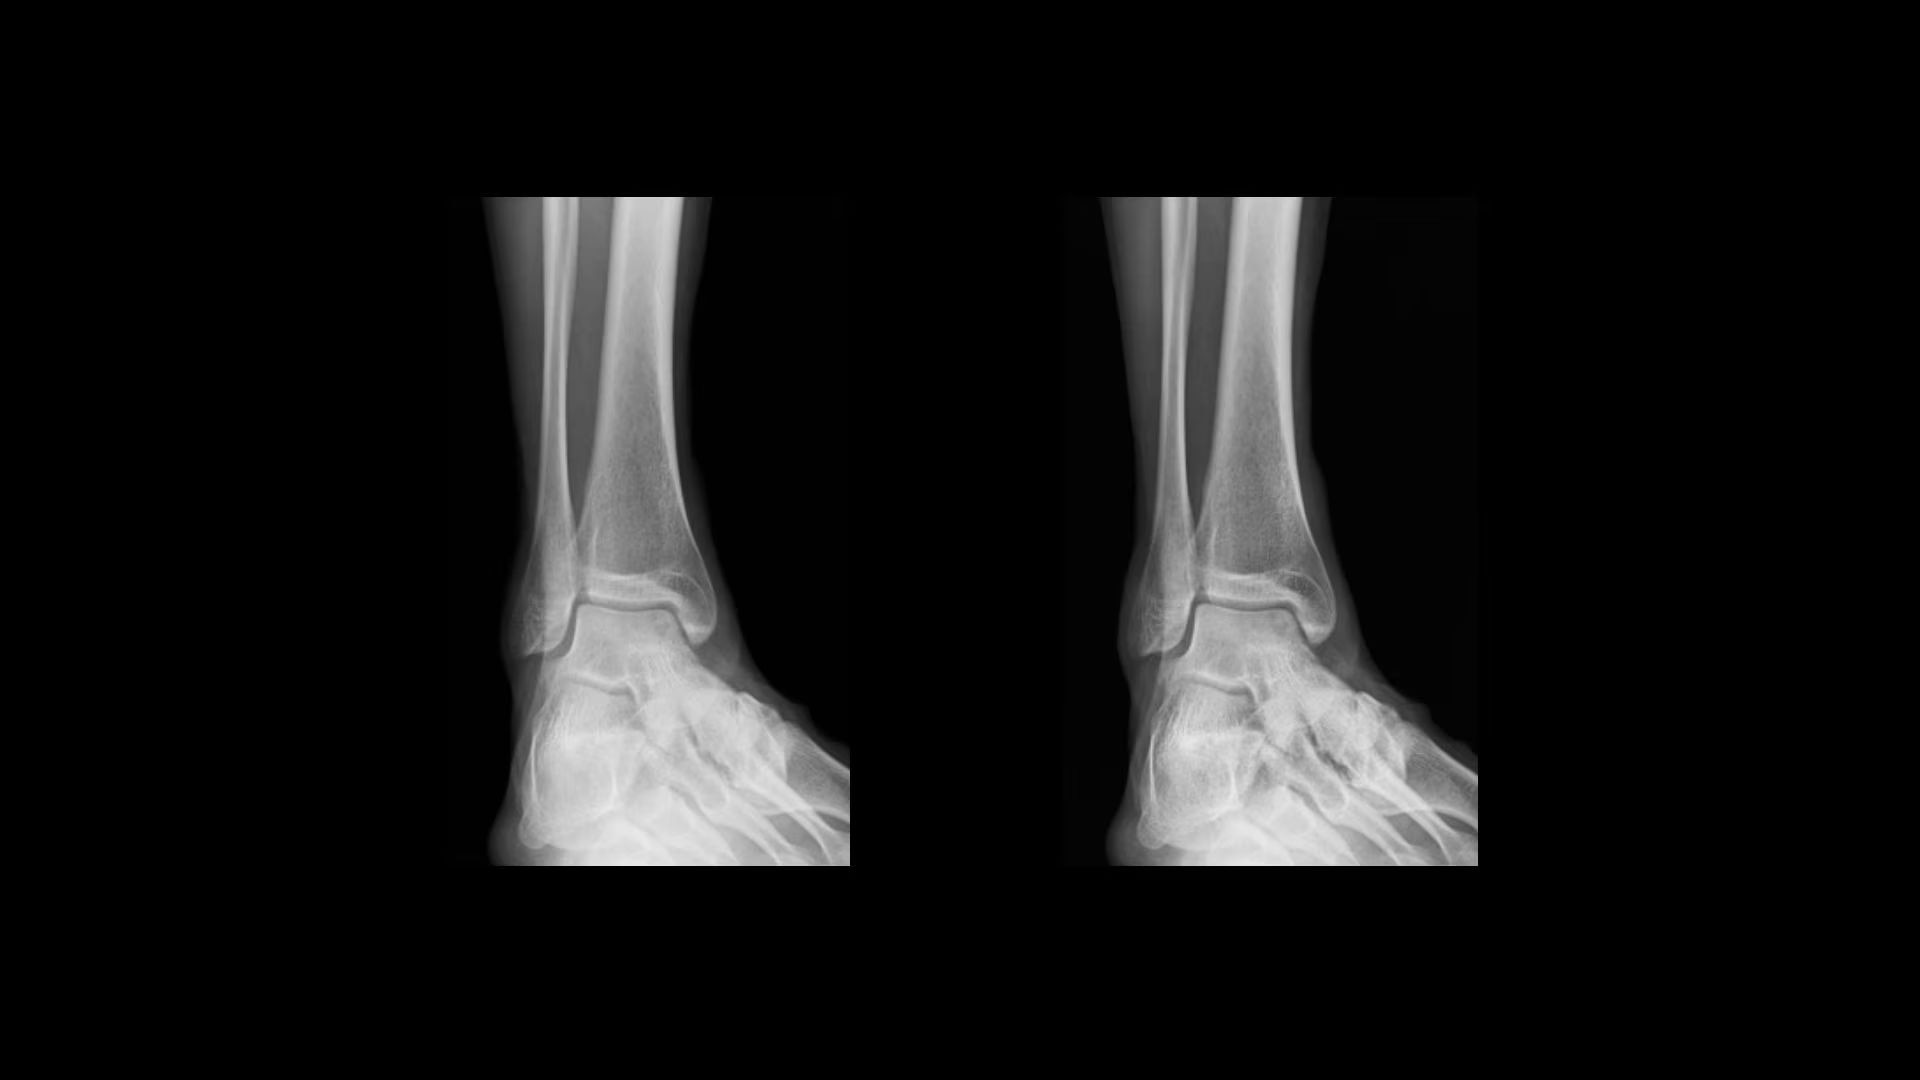

Automated AI Brightness and Contrast (AIBC)

delivers consistent brightness and contrast for 56* anatomy and view combinations regardless of variations in dose, patient positioning, field of view and metal implants. By automatically adjusting brightness and contrast to a user-defined preference, Helix's AIBC can help reduce technologist image processing time by up to 87%.¹